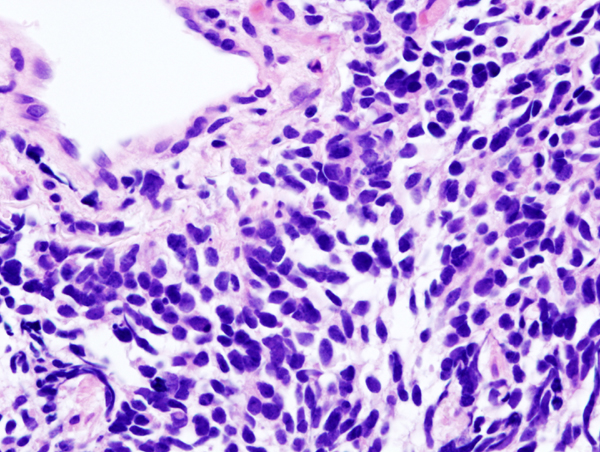

Bladder cancer is the sixth most commonly diagnosed cancer in the United States, according to the NCI. More than 90 percent of the 80,470 new cases of bladder cancer expected to be diagnosed in the United States in 2019 will be classed as urothelial carcinomas because they will arise in cells that comprise the transitional cell urothelium that lines the bladder.

Research, including a paper published in the AACR journal Clinical Cancer Research, has shown that up to 30 percent of urothelial carcinomas have an alteration in one of the four FGFR genes, with the most common alterations being mutations in the FGFR3 gene. These data suggest that targeting FGFRs might provide a new approach to treating urothelial carcinoma.